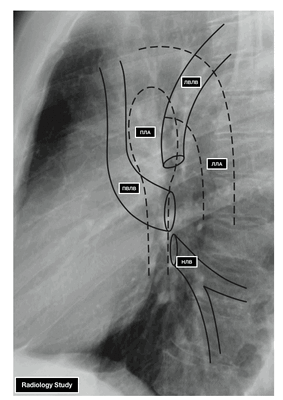

Представлена рентгенограмма правого лёгкого в боковой проекции с указанием топографии междолевых щелей.

- ЛВЛВ — левая верхняя легочная вена

- ПВЛВ — правая верхняя легочная вена

- НЛВ — нижняя легочная вена

- ПЛА — правая легочная артерия

- ЛЛА — левая легочная артерия

У левого легкого сверху находится легочная артерия, кзади и книзу от нее — левый главный бронх. У правого легкого легочные вены лежат ниже артерии, следуют почти горизонтально и на своем пути к сердцу располагаются позади верхней полой вены, правого предсердия и восходящей части аорты. Обе левые легочные вены, которые несколько короче правых, находятся под левым главным бронхом и направляются к сердцу также в поперечном направлении, кпереди от нисходящей части аорты. Правые и левые легочные вены, прободая перикард, впадают в левое предсердие (их конечные отделы покрыты эпикардом).